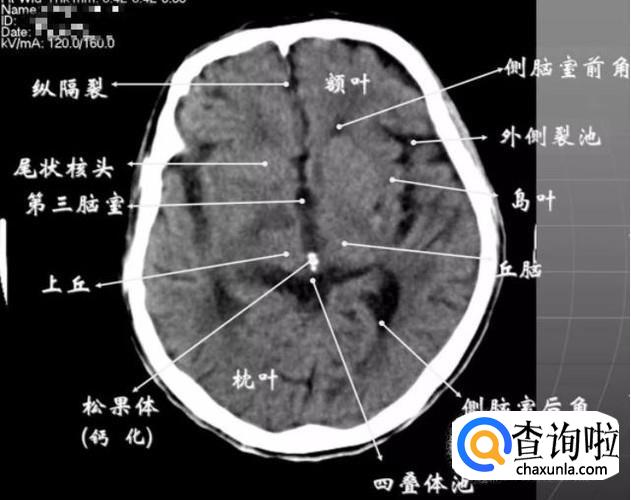

第三脑室上部层面

① 基底核、丘脑。

② 内囊前脚(前肢);尾状核和豆状核之间。

③ 内囊膝部和后脚(后肢):位于豆状核(由外侧的壳核和内侧的苍白球组成)及丘脑之间。

④ 壳核的外侧:外囊、屏状核、最外囊、岛叶(脑岛)。

⑤ 四叠体池:两侧枕叶之间,池内有松果体,向前与第三脑室连接。